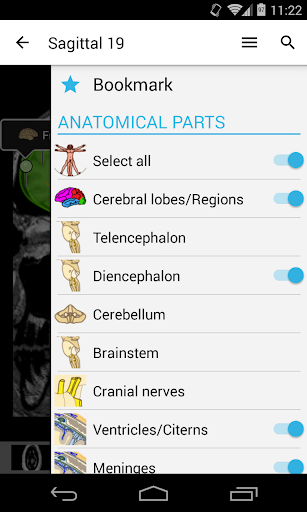

- Seleccione las etiquetas anatómicas por categoría

- Localice fácilmente las estructuras anatómicas gracias a la búsqueda de índice

- Cambie de idioma con solo tocar un botón